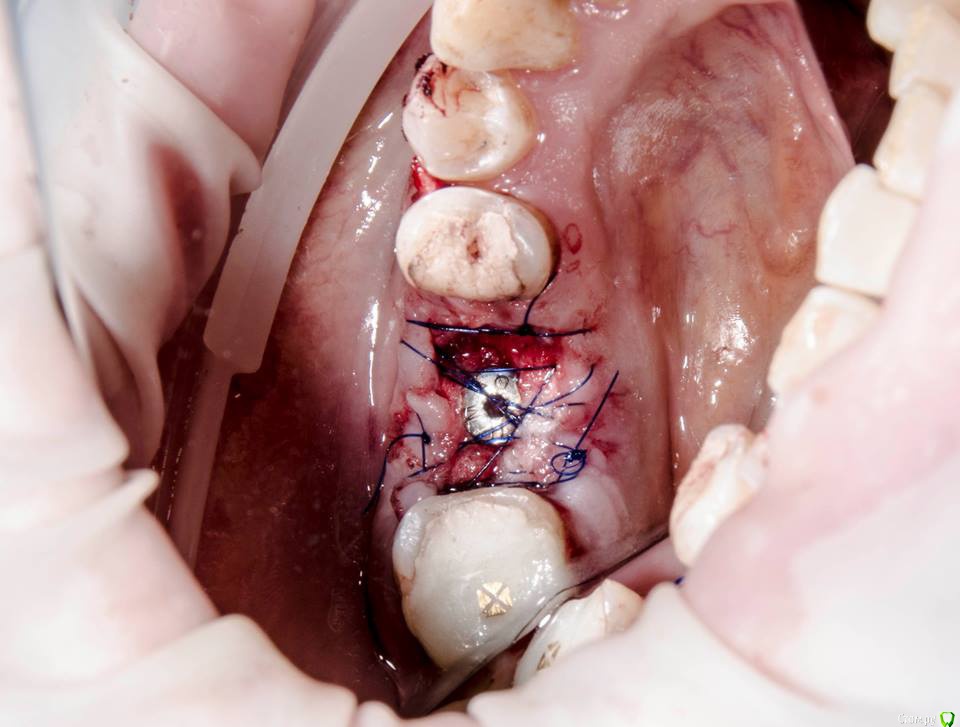

kamranchick Опубликовано 29 марта, 2016 Поделиться Опубликовано 29 марта, 2016 Не надо в рану альвостаз пихать, по опыту он только мешает заживлениюОлег, как вы думаете, можно ли так поступать? тут мембраны нет, только алвостаз Ссылка на комментарий